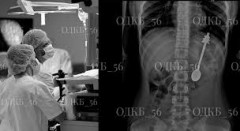

Երեխան կուլ է տվել 14 սմ երկարությամբ գդալ (լուսանկարներ)

Օրենբուրգի տարածաշրջանային մանկական կլինիկական հիվանդանոցի մասնագետները օգնել են 14 սմ երկարությամբ գդալ կուլ տված երեխային։ Այն հանվել է էնդոսկոպիկ եղանակով, և երեխան դուրս է գրվել հաջորդ օրը, հայտնել է հիվանդանոցը։

«Երեխան հոսպիտալացվել է տարածաշրջանային մանկական կլինիկական հիվանդանոցի թիվ 1 մանկական վիրաբուժական բաժանմունքում։ Մասնագետների խումբը, ընդհանուր անզգայացման ներքո, կատարել է շտապ էզոֆագոգաստրոդուոդենոսկոպիա (ԷԳԴ) և օտար մարմնի՝ 14 սմ երկարությամբ մետաղական գդալի էնդոսկոպիկ հեռացում։ Հետվիրահատական ​​շրջանն անցել է առանց որևէ խնդրի, և երեխան հաջորդ օրը դուրս է գրվել տուն՝ բավարար վիճակում», – ասվում է հայտարարության մեջ։